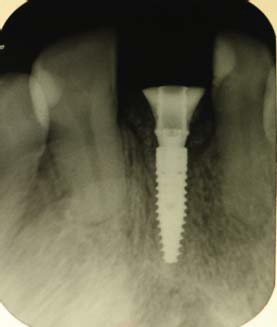

A paciente ERL, gênero feminino, 28 anos, procurou atendimento relatando dor na região anterior superior, com histórico de trauma prévio durante a mastigação. Na avaliação da paciente, o dente 21, aonde havia uma coroa cerâmica instalada com núcleo metálico, apresentava uma fratura obliqua, gengiva edemaciada, com sinais clínicos de infecção na parede vestibular do alvéolo (figura 1 e figura 2). O plano de tratamento incluiu a indicação de exodontia do dente 21, seguida de um implante imediato (Straumann® Bone Level SLActive) associado a um cicatrizador personalizado para manter a caracterização do contorno gengival do elemento.

Simultaneamente, foi realizada a exodontia do elemento 21, seguida da instalação do implante com toque final de 30N. O espaço alveolar remanescente foi preenchido primeiro com o enxerto de conjuntivo associado a uma membrana de colágeno reabsorvível (GenDerm – Baumer), juntamente com material de substituição óssea (Geistlich Bio-Oss, Geistlich Pharma) (figura 7 e figura 8).

Finalizado toda a parte cirúrgica foi feito o posicionamento de um cilindro provisório e da tampa de cobertura que havia sido confeccionado no gesso e feita a união com resina tipo flow, seguindo do acabamento e polimento fora da boca. Uma vez pronto o cicatrizador personalizado, este foi instalado com o torque de 15N e uma prótese parcial removível provisória foi instalada (figura 9, figura 10, figura 11, figura 12, figura 13 e figura 14).